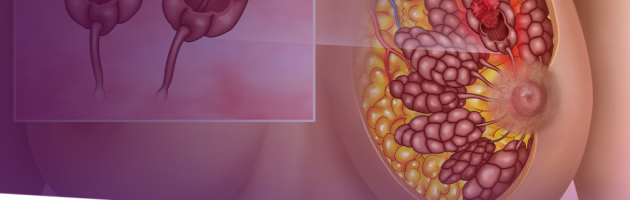

Implante de silicone causa câncer de mama?

Não espere o Outubro Rosa. Faça seus exames de mama regularmente

Brasil registra 600 casos de câncer de mama em homens